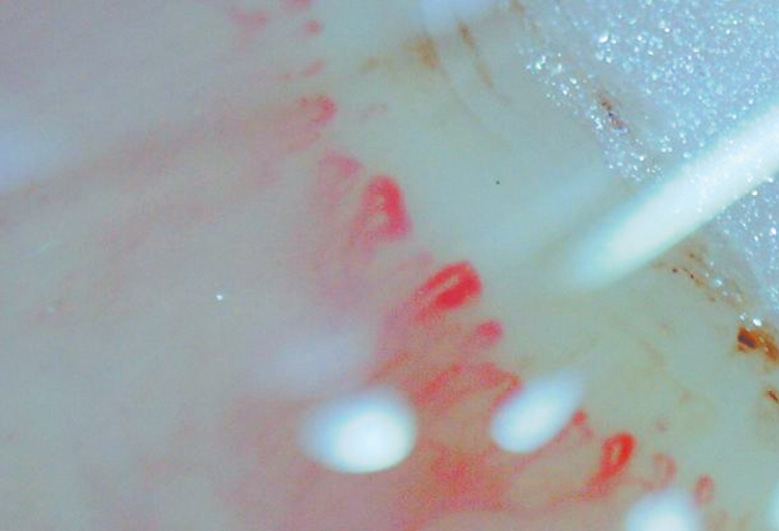

In the comparison groups, the capillaroscopic pattern was represented by single pathological changes in the capillaries that did not indicate pathognomonic sclerodermic patterns, except for the group with dermatomyositis/polymyositis where significant Raynaud’s syndrome was diagnosed in two patients (Figs. 6–9).

Fig. 6. Pathological changes of the capillary bed in the group of patients with idiopathic pulmonary hypertension

Рис. 6. Патологические изменения капиллярного русла в группе пациентов с идиопатической легочной гипертензией

In 13 patients with idiopathic pulmonary hypertension, NFC revealed capillary dilatation (n = 7) and pathological tortuosity and microhemorrhages (n = 4) in all study fields. These abnormalities may be associated with microangiopathy that occurs with endothelial dysfunction or damage due to an imbalance between vasodilation and vasoconstriction.